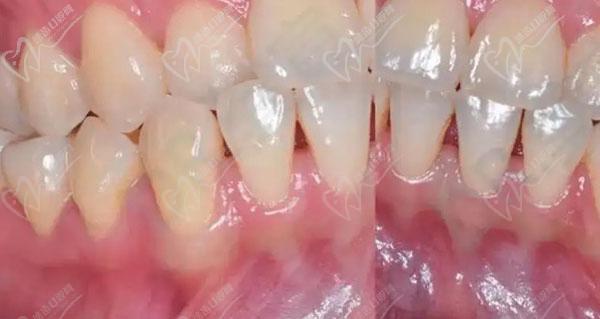

正畸治疗依赖牙槽骨的改建能力:牙齿移动时,牙槽骨一侧吸收、一侧增生,若骨量不足,吸收速度可能超过增生速度,导致牙根暴露、牙齿松动,甚至骨开裂,对于中重度牙槽骨薄患者,正畸前需通过CBCT等影像学评估骨量,判断是否需要植骨,轻度骨薄可通过轻力移动、延长矫正周期等策略调整,但中重度骨薄(如骨厚度<1mm)则需植骨增加骨量,为牙齿移动提供足够支持。

植骨时机需个体化设计:常见方案有三种,一是正畸前植骨(引导骨再生GBR),先植骨等待3-6个月骨结合完成后再正畸,适用于骨量严重不足者;二是正畸中植骨,在牙齿移动过程中同步进行局部植骨,缩短治疗周期;三是正畸后植骨,针对矫正后美学区骨量不足,改善牙龈形态,无论哪种方案,术后均需保持口腔卫生,避免咀嚼硬物,定期复查骨愈合情况。